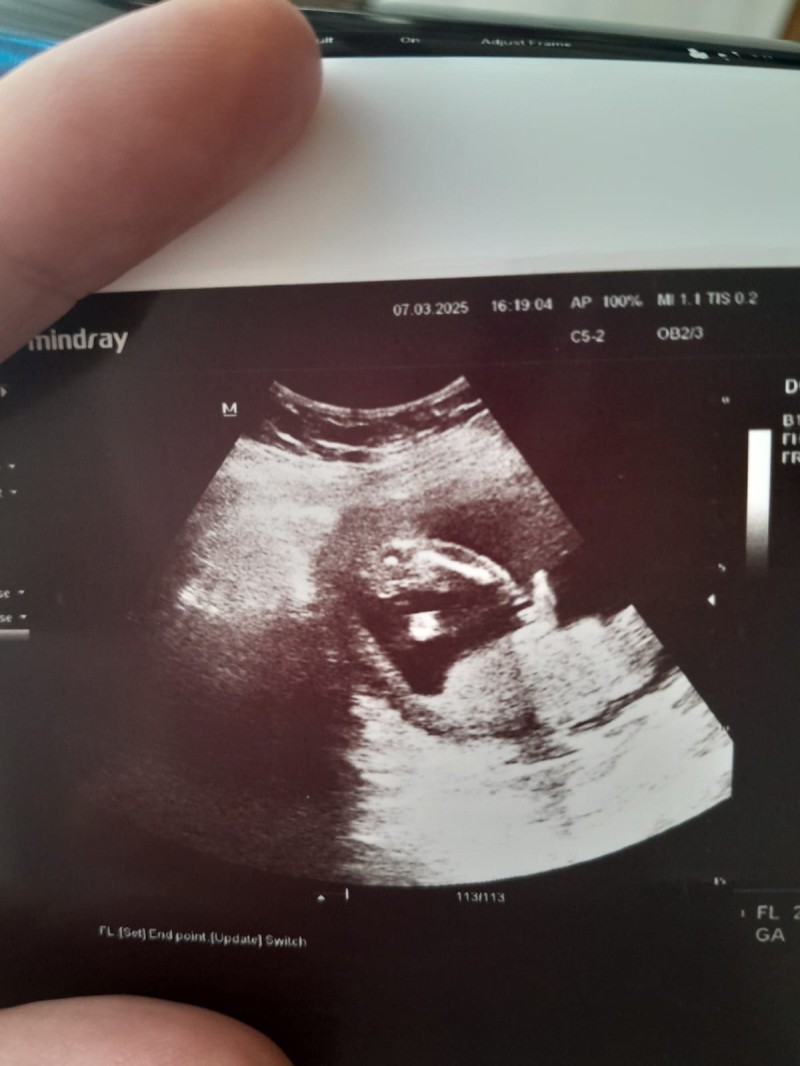

Arkadaşlar bu resimdeki ne ultrasonda anlayan var mı bakıyorum bakıyorum anlamıyorum bebek ki bacak mi pipi mi kordon mu bi türlü anlayamıyorum

Bu resim 16+6 haftaya ait erkek dedi bir hafta öncesinde de kordonmus kız bebek demisti başka doktor

Resimde hiç birşey belli olmuyor

Ben acaba o şey pipi mi diye düşündüm de anlamadığım için